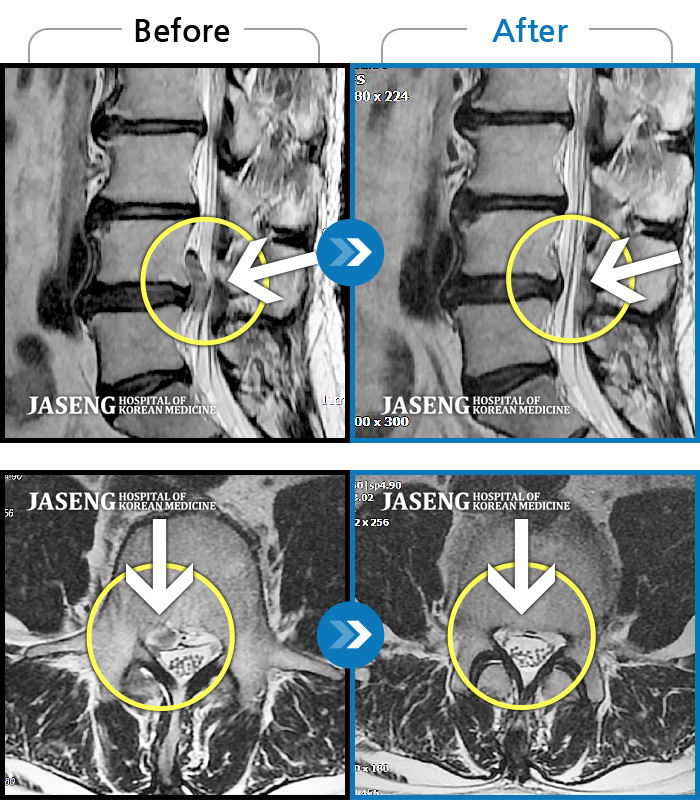

MRI 치료사례

우측이 주로 뻐근하고 뭉친 느낌이 든다. 앉아있으면 허리가 묵직하고 목에도 무리가 와서 앉아 있을 수가 없음.